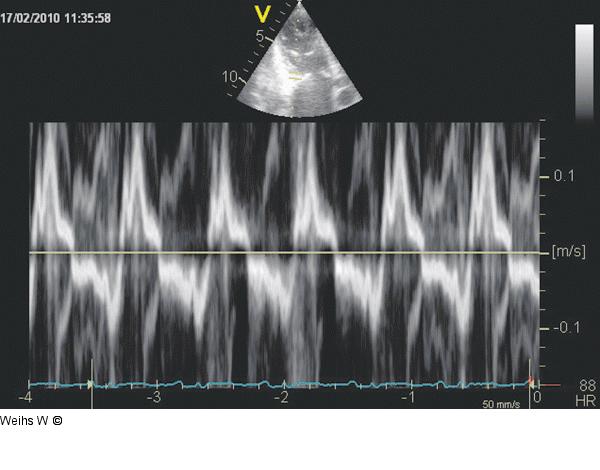

Abbildung 10: Tissue Doppler Die systolische Längsverkürzung des rechten Ventrikels als Maß der Pumpfunktion lässt sich im „Tissue Doppler“ (lateraler Trikuspidalring) darstellen |

Die systolische Längsverkürzung des rechten Ventrikels als Maß der Pumpfunktion lässt sich im „Tissue Doppler“ (lateraler Trikuspidalring) darstellen |